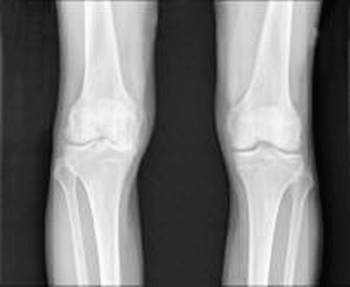

골관절염은 퇴행성 관절 질환으로 사용 정도에 따른 점진적인 관절연골의 소실, 또는 변화되는 증상을 동반합니다. 우리 몸의 관절에는 충격을 흡수하는 관절연골이 있는데요. 이러한 연골의 변화로 관절을 구성하는 뼈, 인대, 관절막 등에 2차적인 손상이 생겨 통증이나 기능 장애를 일으킵니다.

대표적인 증상은 관절의 통증입니다. 특히 무릎의 경우 계단을 오르거나 내릴 때 통증이 심해집니다. 증상이 진행되면 무릎에 물이 차서 하루 종일 통증이 생길 수 있는데요. 척추 관절, 고관절, 손가락 관절 등 다양한 부위에 발생할 수 있고 통증을 동반합니다. 손가락 마디에 발생하는 경우 손가락 마디가 굵어지기도 합니다.